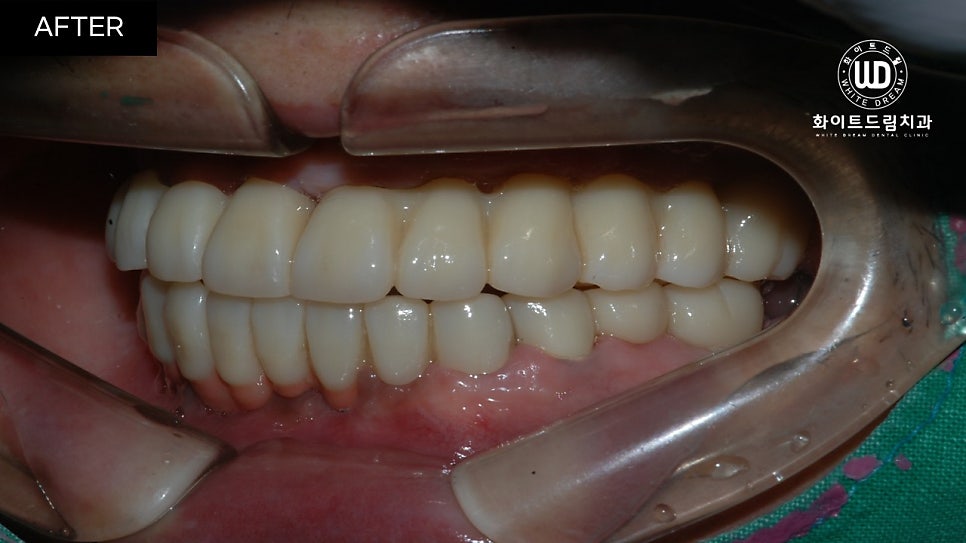

중간 지주대를 픽스처에 연결해주고 2주뒤 최종 보철물까지 올려주니 실제 치아와 비슷하게 기능적, 심미적으로 회복되었습니다.

치아 정면 전/후 사진을 함께 살펴보면, 임플란트 식립 모양이 돔 형태로 예쁘게 이식된 것을 확인할 수 있습니다. 전체 임플란트는 교합면을 잘 선정하는 것이 중요합니다. 교합면은 자연치가 맞물리는 면으로, 너무 높으면 턱관절에 무리가 갈 수 있고 저작할 때 고르게 분산되지 않습니다.

반대로 너무 낮으면 구강 내부 혀나 볼을 씹어 상처가 나고, 턱 모양에도 영향을 끼칠 수 있기 때문에 정밀 검사 후 적절하게 식립하는 것이 좋습니다.